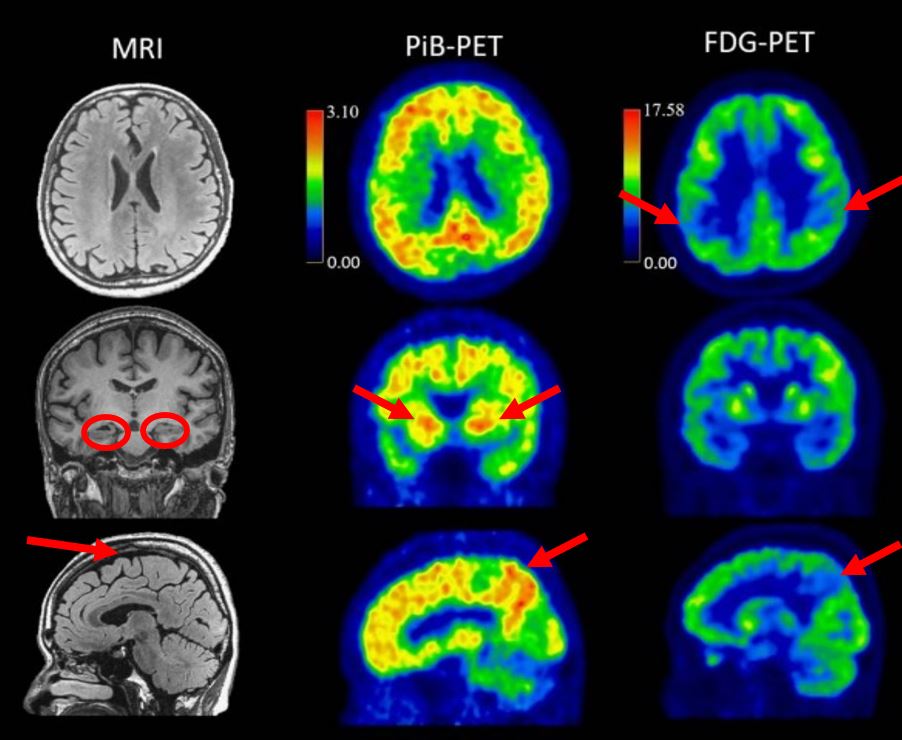

另外,也對32位參與者進行腦部的MRI,我們來看看其中一個案例,瞭解AD患者腦部內的變化,如圖四:

圖四|一位59歲開始發病的AD女性患者,61歲時的腦部MRI影像,以及62歲時的「類澱粉斑塊正子斷層造影(Amyloid PET,也稱PiB-PET)」與「氟化去氧葡萄糖正子斷層造影(FDG-PET)」。

透過腦部MRI,我們可以看到患者在61歲時有輕度內側顳葉及頂葉萎縮的現象。62歲時,透過PiB-PET可以看到其腦部廣泛皮質和紋狀體的類澱粉斑塊沉積,FDG-PET則顯示腦中雙側顳葉-頂葉區域代謝功能降低。